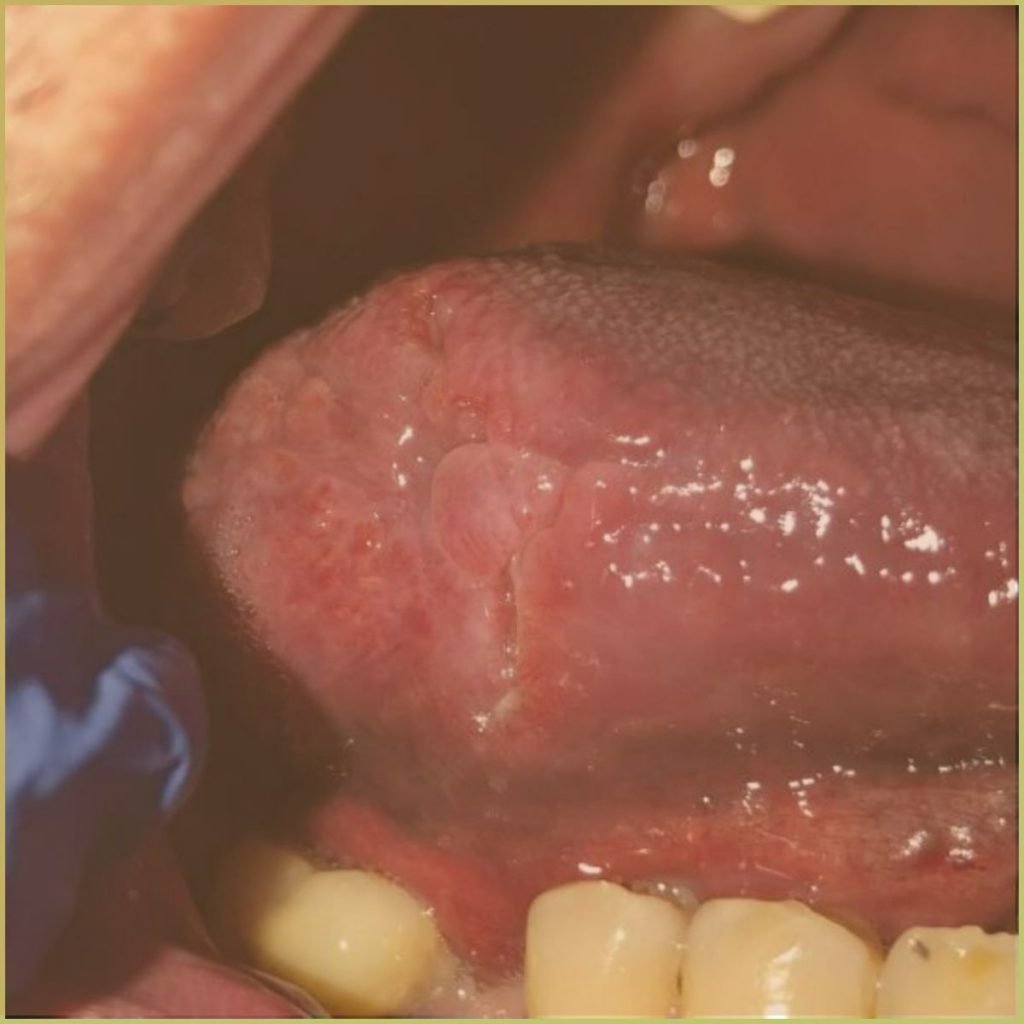

HISTOPLASMOSIS

Histoplasmosis is a fungal infection caused by Histoplasma capsulatum which is endemic to the Ohio and Mississippi River valleys. Transmission is via spore inhalation, leading to pulmonary lesions with possible dissemination to secondary sites. Most infections are subclinical and self-limiting in immunocompetent patients. Organ involvement due to disseminated histoplasmosis can be fatal if untreated. The common clinical presentation includes:

- Chronic ulcerations with necrosis.

- Elevated nodular margins around ulcers that may resemble squamous cell carcinoma.

- A cobblestone appearance on the tongue

Diagnosis is based on the lesion history, clinical presentation and serological findings or culture analysis. Your differential diagnosis should include:

- Tuberculosis.

- Squamous cell carcinoma or other malignancy.

- Other deep fungal infections (coccidioidomycosis, cryptococcosis, and blastomycosis).

- Chronic traumatic ulcer.

- Tertiary syphilis.

- Crohn’s disease.

Treatment options include various antifungal agents (Amphotericin B, ketoconazole, fluconazole, itraconazole). The condition may be self limiting and the prognosis is generally good.